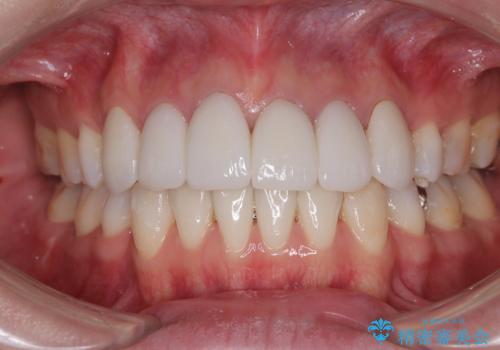

デコボコと銀歯 矯正治療とセラミック治療で綺麗な口元に